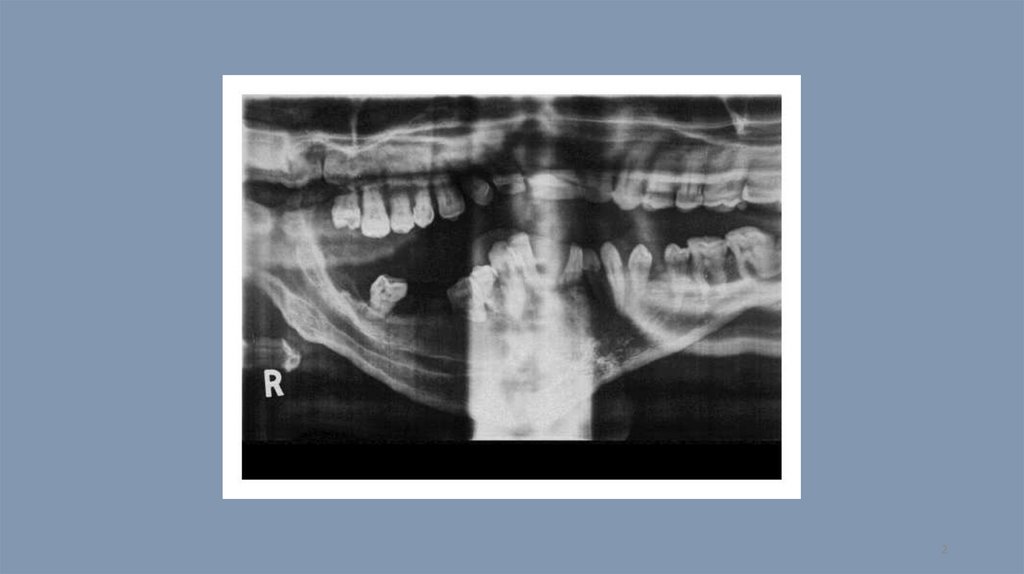

Компьютерная томография. Тест 14